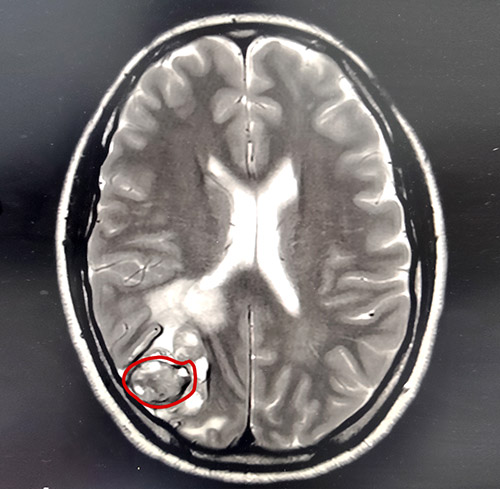

胡女士就是不信这个邪,经多方打听后胡女士辗转来到上海蓝十字脑科医院。在蓝十字脑科医院进行了仔细全面的体检,影像检查提示:左足跟黑色素瘤切除术后,患者颅脑右侧枕叶皮髓质交界处高密度团块伴周围脑实质水肿,考虑为转移瘤。身体其他部位未见明显转移灶。

▲MRI提示右侧顶枕叶皮髓质交界处占位

基于细致严谨的检查评估后,上海蓝十字脑科医院神经外科主任沈建康教授领衔的专家团队一致认为,手术切除患者脑部肿瘤具备条件,且可有效延长患者生存期,提高生存质量。